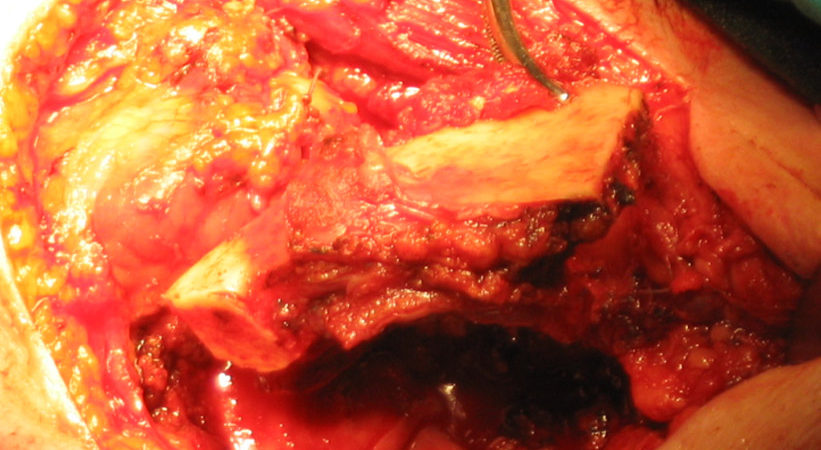

CASO CLINICO N° 2

Donna di 82 anni portatrice di un carcinoma squamoso multifocale del cavo orale infiltrante la mandibla T4N0.

Una mandibulectomia marginale è stata effettuata con tecnica piezoelettrica.